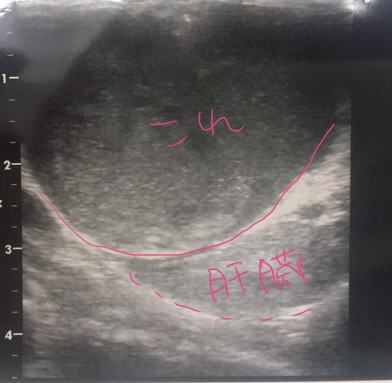

先日病院に行った夜から、お薬はじめたんだけど 食欲もがたっとへって、フードをほぼたべてくれなくなってしまった はなちゃんです。 6月に入って、それまでふやかしフード15~25gくらい食べてくれてたのが 4日から8~13gくらいに減り、でもコオロギやゼリーなどのはなちゃん的に好きなものは 食べていてくれたんですけど、 22日に口の奥の腫れが気になって病院に行った後は フードは0~3g、ゼリーはそれなり食べてくれる、コオロギは元々去年の歯肉炎の時から 頭部のかたいところは切除してやわらかいおなかのところだけあげてたんですが それも外皮部分?をくちゃくちゃやったあとぺっと出すように。 何か食べて貰わないとと思って最近あげてなかったゆで卵の黄身をあげたら ちょっと食べてくれました。 ササミをゆでてミキサーでスープ状にしたのは、最初こそなめてくれたけど 最初以外は興味なくしてしまったみたい… 余りに食べないせいなのか、他に要因があるのか 23日からは左後ろ足が思うようにうごかなくなってきているぽくて ふらつきながら歩く、もしくは左側にぺたっと尻もちをつくというかんじ。 ダックスープを昨日材料届いたので作って出したけど、やっぱりいちど舐めてからは 興味を失ったっぽい。 なので、今朝シリンジでダックスープを少しうすめたものを強制的に口に入れてみたんだけど 最初の一回はとりあえずなめるけど、2回目はもう顔をそむける身体全体で嫌がる、で 食べるということをしたくないのかな~と…身体に食料を入れたくない? 一応25日にみわさんに電話してお薬のせいもあるのかと相談してみたけど それは考えづらいといわれつつ、様子見るために、26.26日とお薬やめてみたけど 薬のせいじゃないっぽい…。 足のふらつきが、最後の方のかのたんを思い出させて うーむ…と思うのですが 食べる事にわりと貪欲なはなちゃんがそれを嫌がるくらいだし ここ一年くらいずっと治療で手術も乗り越えて半年以上たつし、 もうあとは無理にどうこう治療するよりはなちゃんの好きなようにして貰った方が いいのかなあ…なんて考えたりもしています。 食欲が戻ればまた元気になってくれるのかなあ…。 とりあえず食べて貰えるようにいろいろまた試行錯誤します。 そんな近況です。 |